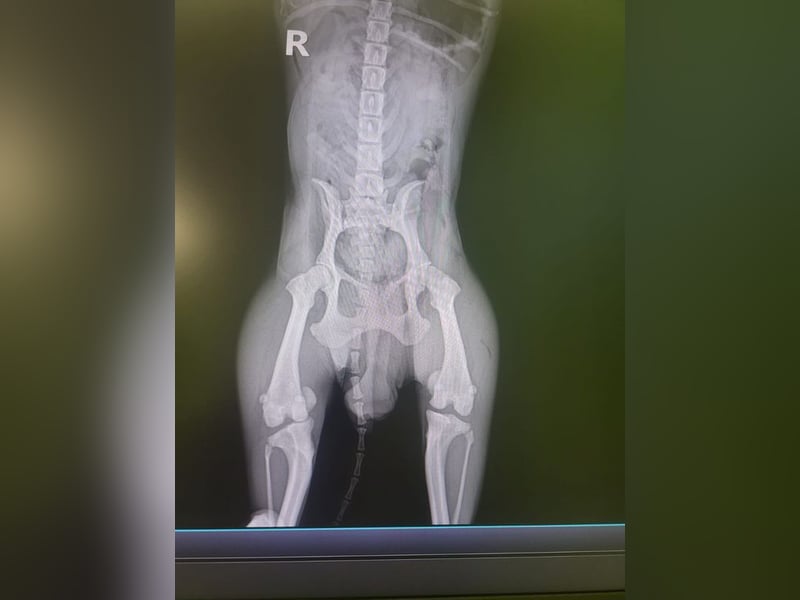

Bemerkungen: Bei Carmen entwickelt sich auf beiden Augen ein Hornhautgeschwür, das medikamentös behandelt wird. Sie hat Osteoporose im linken Hüftgelenk, der linke Rippenbogen wurde operiert und drei Zähne entfernt. Beim Röntgen wurde eine Verschattung der kranialen Bronchien festgestellt, und sie hat eine anbeborene Fehlbildung der Kniescheiben.

Carmen verbrachte ihr Leben in einer Vermehrerstation. Sie wurde den Tierschützern angeboten, und wir denken, dass diese „freundliche“ Geste dann doch wohl eher mit dem gesundheitlichen Zustand von Carmen zusammenhängt. Bei Carmen entwickelt sich auf beiden Augen ein Hornhautgeschwür. Als medizinische Anwendung bekommt Carmen momentan 2 x täglich Corneregel. Ferner hat sie Osteoporose im linken Hüftgelenk. Ihr wurden drei Zähne entfernt und der linke Rippenbogen operiert. Der Thorax wurde geröntgt und eine Verschattung der kranialen Bronchien festgestellt, ferner eine angeborene Fehlbildung der Kniescheiben.